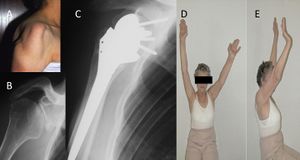

Reverse shoulder arthroplasty is a more reliable treatment than hemiarthroplasty for complex proximal humerus fractures at least in elderly patients because its functional outcomes appear to depend less on tuberosity healing and rotator cuff integrity (Figure).[90]

Reverse shoulder athroplasty for fracture. Frontal, axial and lateral Lamy radiographs after a reverse total shoulder implant. Note the lower positioning of the glenoid baseplate, the satisfactory reconstruction of the tuberosities, and the absence of cement at the autograft level.

Reverse shoulder arthroplasty for malunion of proximal humeral fracture. A) Anteroposterior radiograph of a malunited proximal humerus fracture; B) post-operative radiograph of the fracture sequelae treated with reverse shoulder arthroplasty.

Locked dislocation of a right shoulder. On the right, postoperative X-ray.

Revision surgery after primary shoulder arthroplasty (i.e. hemiarthroplasty, resurfacing or total shoulder arthroplasty) produced high patient satisfaction (Figure). It is, however, associated with higher complication and failure rates compared to reverse shoulder arthroplasty for patients without previous arthroplasty.[93]

A) Anteroposterior radiograph of a failed anatomic total shoulder arthroplasty; B) Anteroposterior post-operative radiograph after reverse shoulder arthroplasty.